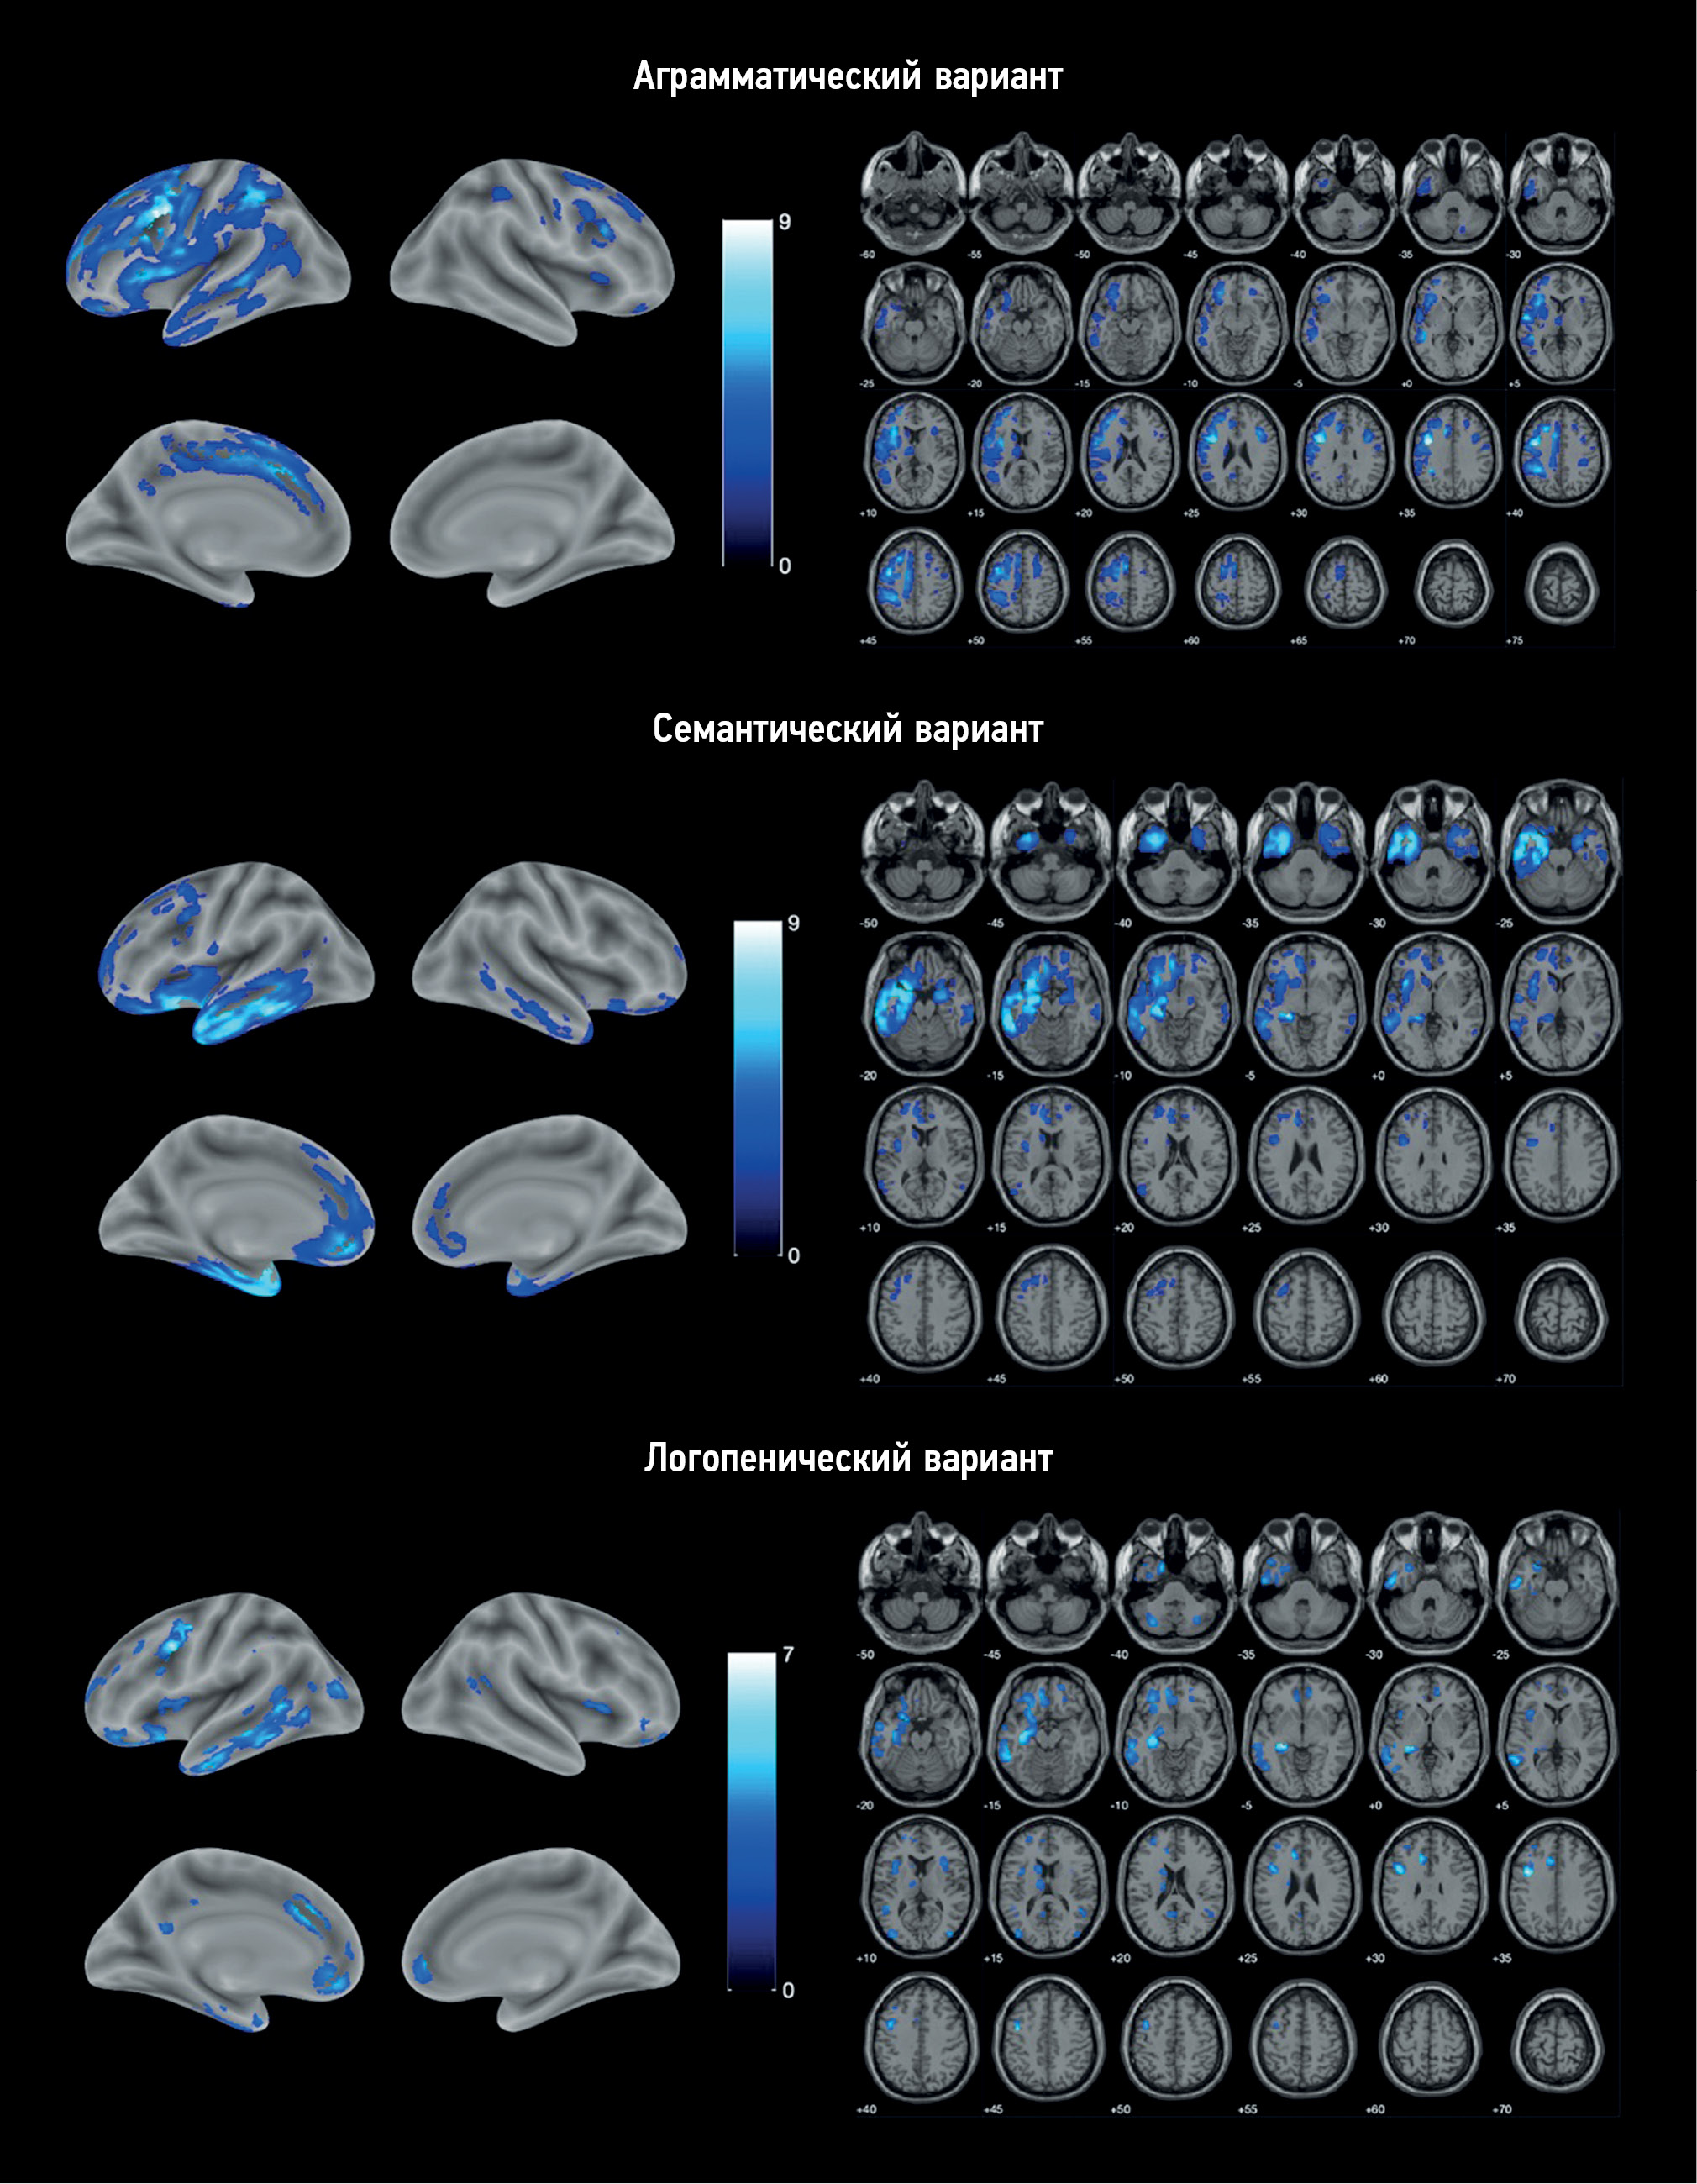

VBM identified areas of atrophy in each PPA variant compared with the control group (Fig. 1). Atrophy in all cases was asymmetric, prevailing in the left hemisphere.

Fig. 1. Localization of the areas of the loss of the gray matter volume in variants of primary progressive aphasia vs. control group. The color coding is for the T-value.

AV-PPA group: The atrophic “core” was localized in the left IFG and precentral gyrus (Table 2). Significant changes were also observed in the SMA, premotor cortex, orbitofrontal cortex (OFC), and insular cortex of both hemispheres. The temporal lobe was mainly involved in the MTG and inferior temporal gyrus (ITG), continuing into the area of the temporoparietal junction and inferior parietal lobule. In addition, atrophic involvement of subcortical structures was observed, namely, the left caudate nucleus, thalamus, putamen, and cerebellum.

SV-PPA group: Atrophy was predominantly localized in the left temporal lobe, including its pole, inferior–lateral and medial regions, and left hippocampus and insula (Table 3). Individual lesions were observed in the left frontal lobe, including the OFC, medial prefrontal cortex (mPFC), premotor cortex, precentral gyrus, and IFG. Overall, the changes were more localized than in AV-PPA and were limited to the frontal, temporal, and insular cortices, except for an atrophic lesion in the left caudate nucleus. Similar but less extensive atrophic areas were identified in the right hemisphere.

LV-PPA group: The most pronounced loss of the GM volume was also localized in the left temporal lobe but was mostly involved in the posterior parts of MTG and ITG and, to a lesser extent, the temporal pole. In addition, it continued into the parahippocampal gyrus, hippocampus, and amygdala (Table 4). Atrophy was the most pronounced in the precentral gyrus, anterior cingulate cortex, OFC, and mPFC. Apart from the frontal and temporal lobes, atrophy in this PPA variant involved the insular lobes, left parietal and occipital lobes, cerebellum, and left caudate nucleus.